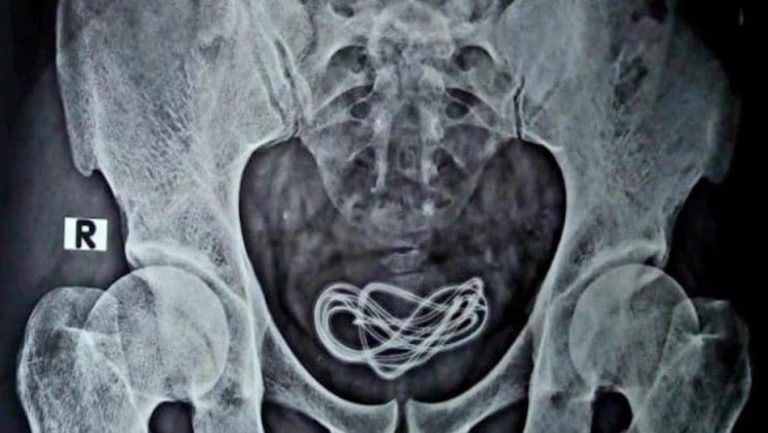

El dolor se hacía más fuerte, por lo que el cirujano y su equipo tomaron una decisión radical. “Como el paciente se quejó de dolor intenso, decidimos realizar una cirugía, descubrimos que no había nada en su intestino”. Entonces una radiografía reveló que el paciente había mentido.

El equipo médico se dio cuenta de que el hombre se había introducido un cable de cargador de teléfono celular por el pene y terminó en su vejiga.

“Hice una incisión allí y saqué el cable, que en realidad era un cable de cargador de más de 60 centímetros de largo”, contó el cirujano.